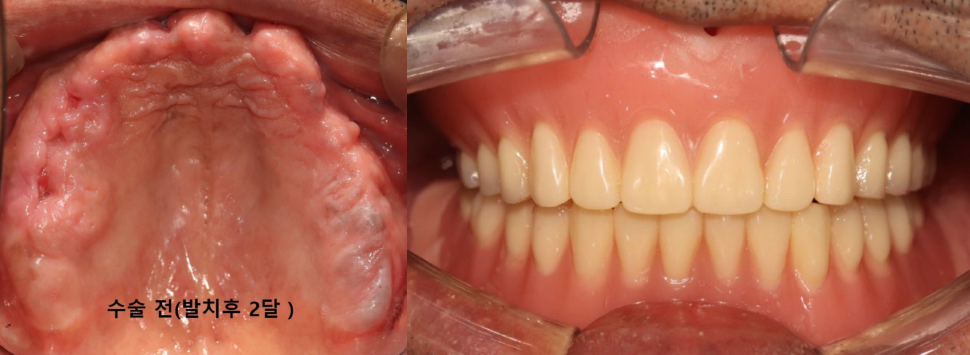

나이가 들면서 전체 치아가 흔들리거나 손상되어 발치 후 전체 임플란트(전악 임플란트)가 필요한 경우가 많아요. 특히 만 65세 이상 환자분들은 평생 1인당 2개까지 임플란트 건강보험 혜택이 적용되니 꼭 확인해 보세요! 이번 증례는 심각한 잇몸 질환으로 모든 치아를 상실한 60대 환자분께서 정교한 맞춤형 전악 임플란트를 통해 건 강한 미소와 저작 기능을 회복한 과정입니다. CASE. 60대 남성 환자, '전체 치아 흔들림'으로 내원 "전체 치아가 흔들리고 아파서 임플란트를 하고 싶어요." 여러 치과를 알아보시던 중, 지인의 소개로 저희 병원을 찾아주셨습니다. 처음부터 전악 임플란트를 염두에 두고, 풍부한 임상 경험을 가진 의료진을 찾고 계셨습니다. 정밀 진단 결과 구강 검진 및 CT 촬영 결과, 환자분의 상태는 매우 심각했습니다. * 구강 상태: 위아래 모든 치아가 심하게 흔들리고, 치아 뿌리가 노출될 정도로 잇몸 조직이 붕괴된 상태였습니다. * CT 및 파노라마 소견: 치아를 지지해야 할 잇몸뼈(치조골)가 염증으로 인해 대부분 소실되어, 치아들이 뼈 속에서 떠 있는 '부유치(floating tooth)' 상태였습니다. 자연치아를 최대한 보존하는 것이 원칙이지만, 이미 치아 뿌리 끝까지 염증이 퍼져 회복이 불가능했습니다. 환자분께 상태를 자세히 설명드린 후, 전체 발치 및 전악 임플란트 계획을 수립했습니다. ![]() ![]() 개인별 맞춤 치료 계획 환자분의 구강 구조와 심미성을 고려하여 아래와 같이 맞춤형 치료 계획을 세웠습니다. * 상악 (윗니): 6개의 임플란트 식립 후 '임플란트 지지 부분틀니 (IARPD)' 붕괴된 앞니 잇몸과 입술의 볼륨감을 심미적으로 회복시키기 위해, 어금니는 임플란트 고정성 보철로 단단히 잡아주고 앞니는 틀니의 잇몸 부분(flange)을 이용해 자연스러운 외모를 재현하는 방식입니다. * 하악 (아랫니): 8개의 임플란트 식립 후 전체 ‘고정성 보철' 전체 치아를 임플란트와 보철물로 단단하게 고정하여 본래 치아처럼 편안하게 사용하는 방식입니다. 치료 과정 1. 발치 및 잇몸 회복 모든 치아를 발치한 후, 염증이 완전히 사라지고 잇몸이 안정될 때까지 약 2개월간 기다렸습니다. 이 기간 동안 환자분의 식사와 심미성을 위해 임시 틀니를 제작해 드렸습니다. ![]() 2. 정확하고 안전한 임플란트 식립 - 상악수술: 잇몸뼈가 얇아 고난도 수술인 상악동 거상술을 동반하여, 계획된 위치에 정확하게 6개의 임플란트를 식립했습니다. 충분한 마취와 정교한 수술, 그리고 숙련된 봉합으로 환자분의 불편감을 최소화하고 빠른 회복을 유도했습니다. ![]() - 하악수술: 최종 보철물의 형태와 기능을 고려하여 적절한 간격과 위치에 8개의 임플란트를 완벽하게 식립했습니다. ![]() 3. 뼈 유착 및 2차 수술 임플란트가 뼈와 단단히 붙는 약 3~4개월 동안 임시 틀니를 사용하며 기다립니다. 이후 모든 임플란트의 ISQ 수치(임플란트 안정성 지수)가 양호한 것을 확인하고, 잇몸 밖으로 임플란트를 노출시키는 간단한 2차 수술을 진행했습니다. ![]() 4. 임시 보철 및 최종 보철 준비 현재는 최종 보철물을 올리기 전, 임시 보철물(PMMA)을 사용하여 환자분이 적응하는 단계를 거치고 있습니다. 임플란트가 완벽하게 식립되었기 때문에 성공적인 최종 결과가 기대됩니다. 전악 임플란트는 단순한 치아 보철을 넘어, 무너진 식생활과 자신감을 회복하는 중요한 치료입니다. 이백점치과는 최소한의 임플란트 식립으로 통증과 불편을 줄이면서도 안정적이고 심미적인 결과를 추구합니다. 풍부한 임상 경험과 높은 환자 만족도로 증명된 실력으로, 치아가 전혀 없는 분들도 다시 편안한 식사와 활짝 웃는삶을 되찾을 수 있습니다. 당신의 현명한 선택, 이백점치과와 함께하세요. |